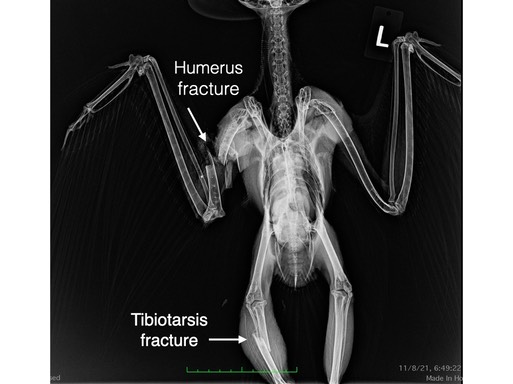

There were just seven admissions this past week, all but one a raptor. Of four Great Horned Owls, three had humerus fractures, the fourth was tangled in a fence, none could be saved. A Sharp-shinned Hawk was shot and a Red-tailed Hawk was likely struck by a vehicle. Neither could be saved. Living in a world filled with humans is no easy task for wildlife.

Great Horned Owl 21-760